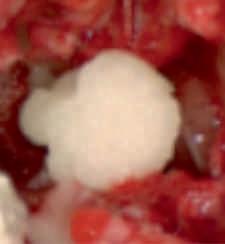

• Absorbable Haemostatic Gelatin Sponge for ENT Use Stops bleeding effectively

• Porous structure and intrices enables high absorption of fluids